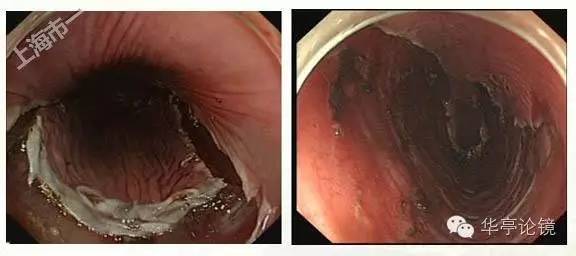

卢戈氏碘染色:病变区多片不染区,形态不规则,见下图。